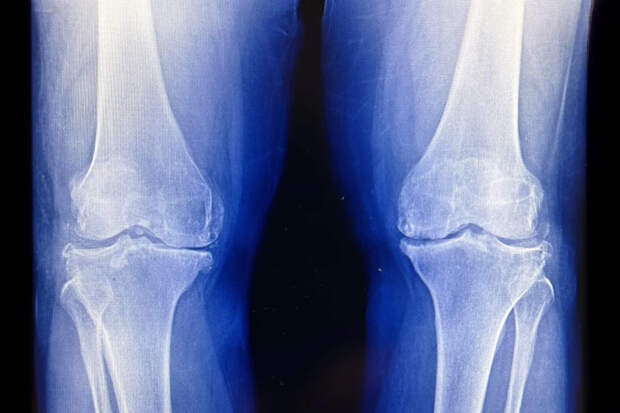

Три грея радиации помогли людям с тяжелым остеоартрозом коленей

Однако на практике население в целом бегать не будет. Поэтому необходимость как-то лечить жертв остеартроза в последние десятилетия постоянно росла, ведь их становилось все больше и больше (так же будет в будущем). При умеренных симптомах дают болеутоляющее, но оно не всегда полностью закрывает проблему и возвращает человеку полную подвижность. Группа корейских ученых привлекла 114 добровольцев с первичным остеартрозом коленного сустава. Диагноз всем им ставился по рентгеновским снимкам и наличию существенной боли при ходьбе. Участников разбили на три группы: первой колени облучали сверхмалыми дозами радиации (шесть сеансов по 0,05 грея), второй — малыми (то же число сеансов по 0,5 грея), третью не облучали ничем. Вторая группа получила локальное облучение, сравнимое с 30 000 рентгеновскими снимками груди или 420 компьютерными томографиями грудной клетки. О результатах исследователи отчитались на ежегодном собрании Американского общества радиотерапии. Никто из участников не мог принимать на регулярной основе опиоидные болеутоляющие или нестероидные противовоспалительные препараты в первые четыре месяца после процедур (или их имитации у группы плацебо). Затем ученые сравнили отзывы членов разных групп о своем состоянии.

Среди тех, кто получил максимум облучения, об улучшениях заявили 70% участников, в группе плацебо — только 42%. Клинические серьезные улучшения в смысле силы боли и функциональности коленных суставов в группе максимального облучения зарегистрировали у 57% участников. Среди получателей плацебо-лечения — только у 31%. Для тех, кто получил лишь 0,3 грея, ситуация была промежуточной: 58% заявили об улучшении состояния, но вот клинические серьезные улучшения по сравнению с группой плацебо врачи не зафиксировали. Как и участники двух других групп, получатели плацебо не имели изменений в составе крови или в уровне маркеров воспалительных процессов. Никаких побочных эффектов от лечения найти не удалось. Это отличает картину от радиотерапии при раке, где локальные дозы в десятки раз выше трех грей и без побочных эффектов сложно обойтись. Авторы научной работы продолжили отслеживать состояние облученных, сейчас идет 12-месячный цикл мониторинга. По его итогам запланировали публикацию. Как отметили разработчики метода, он не сможет регенерировать хрящевую ткань в коленном суставе, если она уже утрачена. Но пока речь идет об умеренной или средней силе остеоартроза, такой подход способен серьезно замедлить развитие болезни. Положительное воздействие умеренных доз радиации на ткани человека ученые выявили довольно давно. Naked Science ранее писал об эффективном поддерживающем лечении болезни Альцгеймера у людей небольшими дозами облучения, а для мышей, облученных более серьезными дозами, удалось полностью развернуть развитие болезни, восстановив их когнитивные способности до нормального уровня.